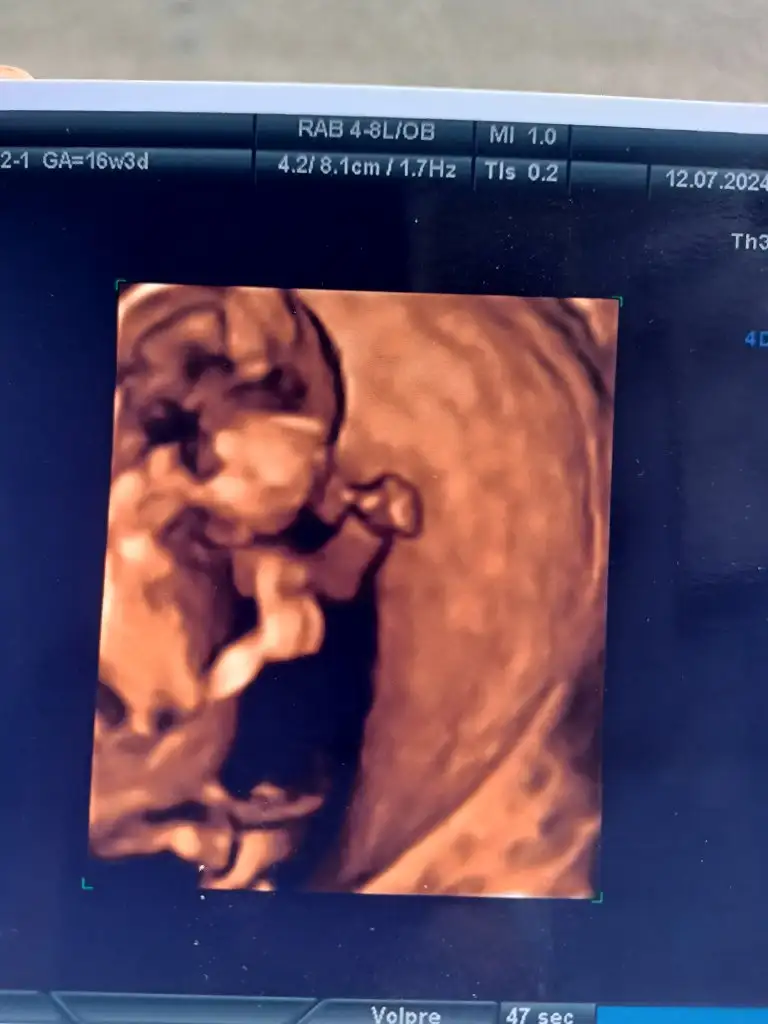

Na bi şu çüküsü belli 😅

IMG_20240712_115036.webp